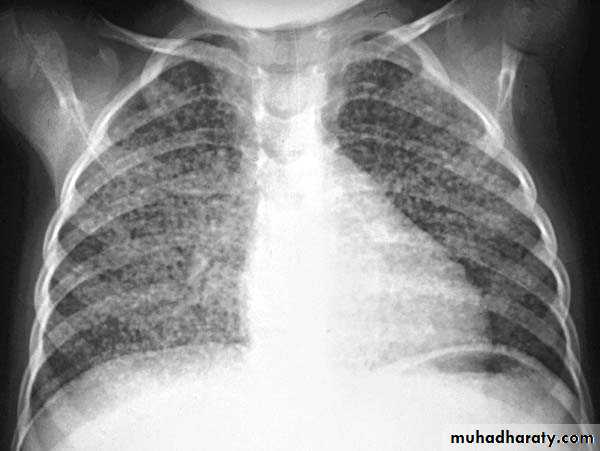

Lobular consolidation ( broncho pneumonia )

Very important to consider that pulmonary edema in normal sized heart have close similar appearance to broncho pneumonia

The important Golden Key differentiation is the cardiac size being enlarged in pulmonary edema .

36.lobuler consolidation (lobular pneumonia )37.discussion